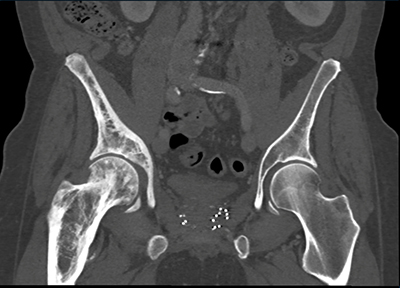

The best diagnosis in this patient with abdominal pain is?

metastatic prostate cancer

lymphoma

Pagets disease

metastatic breast cancer